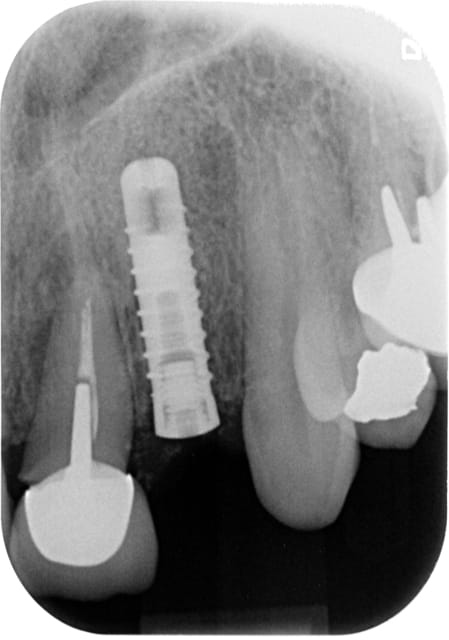

Voila: extraction curetage, implantation à 1 semaine, tranquille.

Le col de la prov est volontairement un peu étroit pour éventuellement faire un "Bichacho" plus tard.

Rom1 wmgjgx - Eugenol

Rom2 yakwup - Eugenol

Rom j14 hiy9ln - Eugenol

Longueur =16. Je n'avais pas de scan, mais j'avais la racine, elle fait 10, 3mm de granulome, il faut plus long si on aime les implants "minces" (ça c'est un autre débat)